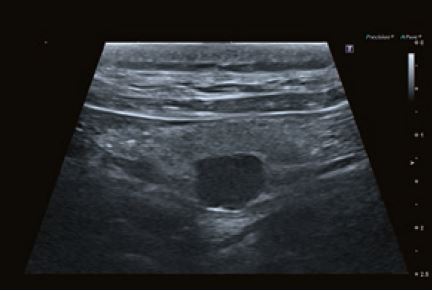

Випадок 1

Собака з гіперкальціємією, спричиненою аденомою паращитоподібної залози справа, яку можна розпізнати як гіпоехогенне, добре відмежоване утворення, що піднімається над поверхнею щитоподібної залози.